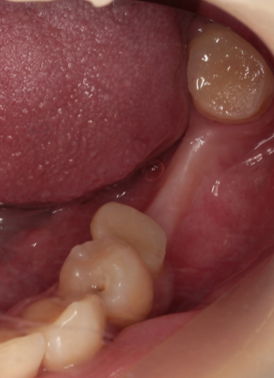

通常抜歯後、顎の骨は吸収する。後のインプラント治療が不利になる。抜歯前の疾患により歯を支える骨を失っており、即時埋入が難しい場合に行っている。

32歳女性